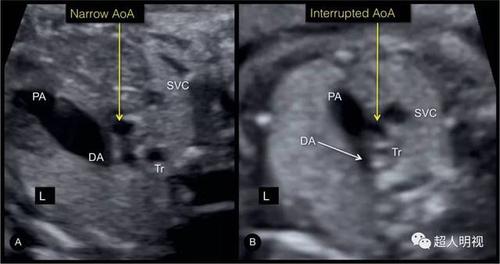

三血管-气管切面可见畸形

三血管气管切面异常